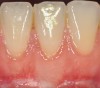

The workshop's group on periodontal soft-tissue root coverage procedures evaluated the predictability of root coverage procedures for single- and multiple-tooth Miller Class I and II10 periodontal recession defects. The workshop concluded that predictable root coverage was possible for Miller Class I and II recession involving a single tooth. When compared with the use of acellular dermal matrix graft (ADMG) (donor tissue) or EMD (porcine origin), procedures using a subepithelial connective tissue graft (SCTG) harvested from the patient's palate provided the best root coverage outcomes in conjunction with a coronally advanced flap.11 As alternatives to autogenous donor tissue, the workshop found strong evidence to support the use of an ADMG or EMD in conjunction with a coronally advanced flap and limited evidence to support the use of platelet-derived growth factor and xenogeneic collagen matrix.11 In addition, root coverage procedures were found to be effective for Miller Class I and II recession defects affecting multiple teeth, although the evidence is limited.11 Figure 1 and Figure 2 show the pretreatment and 1-year postoperative views of a soft-tissue root coverage treatment with SCTG and EMD that used a coronally advanced flap and a tunneling procedure. Figure 3 and Figure 4 depict the pretreatment and 3-year postoperative views of a root coverage procedure with ADMG and EMD that used a coronally advanced flap and a tunneling procedure (this patient was noncompliant following surgery and did not return to the office until the 3-year postoperative appointment).

(3.) Pretreatment view of recession affecting multiple maxillary teeth.

Figure 3